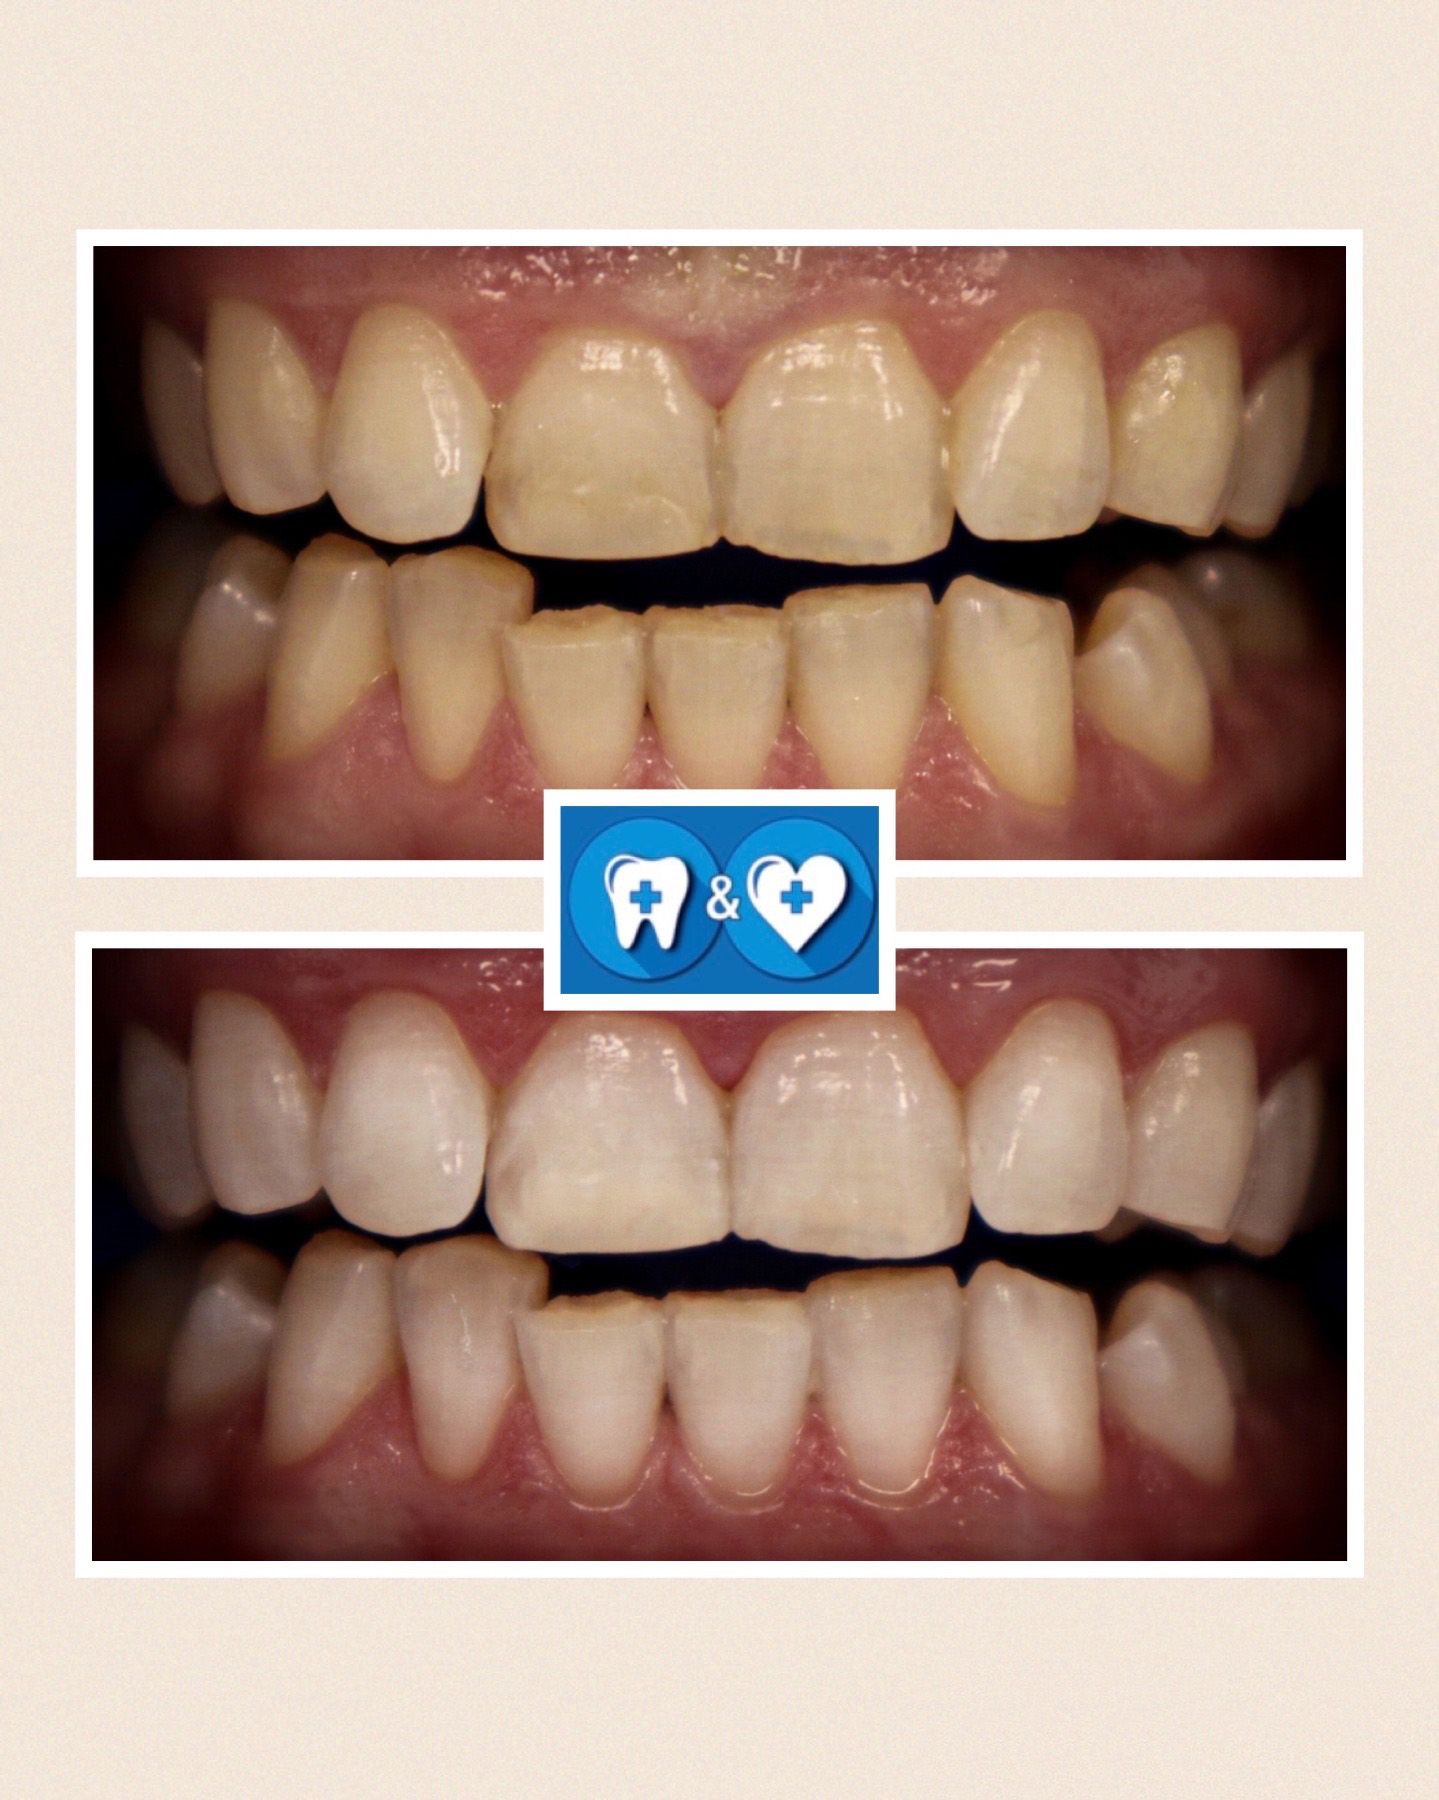

Specialiais instrumentais ir ultragarsiniu skaleriu pašaliname ant dantų susikaupusius akmenis. Su smėliasrove ir perlų soda nuvalome tabako, arbatos, kavos, vyno apnašas.

Dantų poliravimas su soda, E-FLOW technologija leidžia pašalinti atsiradusias pigmentines dėmes!

Po burnos higienos procedūros dantys bus daug gražesni ir baltesni! Ir sveikesni!